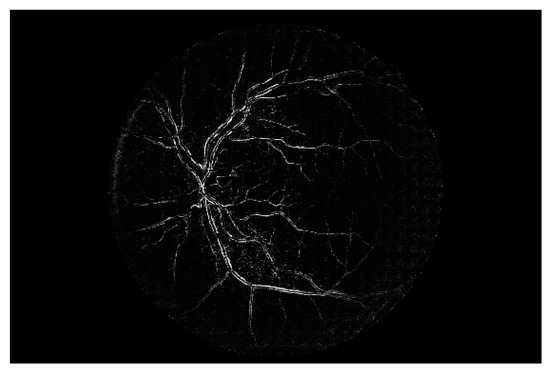

Figure 4. Retinal vessels of Figure 2.

Retina images are digital images of the interior of the eye, specifically the rear portion. Retina images are required to show the retina, optic disk, and blood vessels, as shown in Figure 2. Figure 2 shows a retina image from the digital retinal images for vessel extraction (DRIVE) [59] dataset, which is often used in retina-related studies.

The techniques that are often used for automating retinal vessel segmentation are based on machine learning [28,29,30,31,32,33,34,35,36,37,38,39,40,41,42,43,44,45,46]. This is because replacing the lost vessel portion of an original retina image with another person’s vessels lacks ethical credibility. On the other hand, machine learning is credible because it learns patterns in which people’s vessels are spread. The focus of most recent studies is on deep learning-based supervised learning, and this is the same for retinal vessel segmentation automation. To learn vessel images, masks must be prepared in advance for the vessel portion. Figure 4 shows the manually prepared vessel portion of Figure 2. Moreover, the areas of the vessels must be specified when the dataset’s retina images are in a different environment (minor changes in position that occur when the image is captured). Figure 5 shows the position mask for Figure 2.